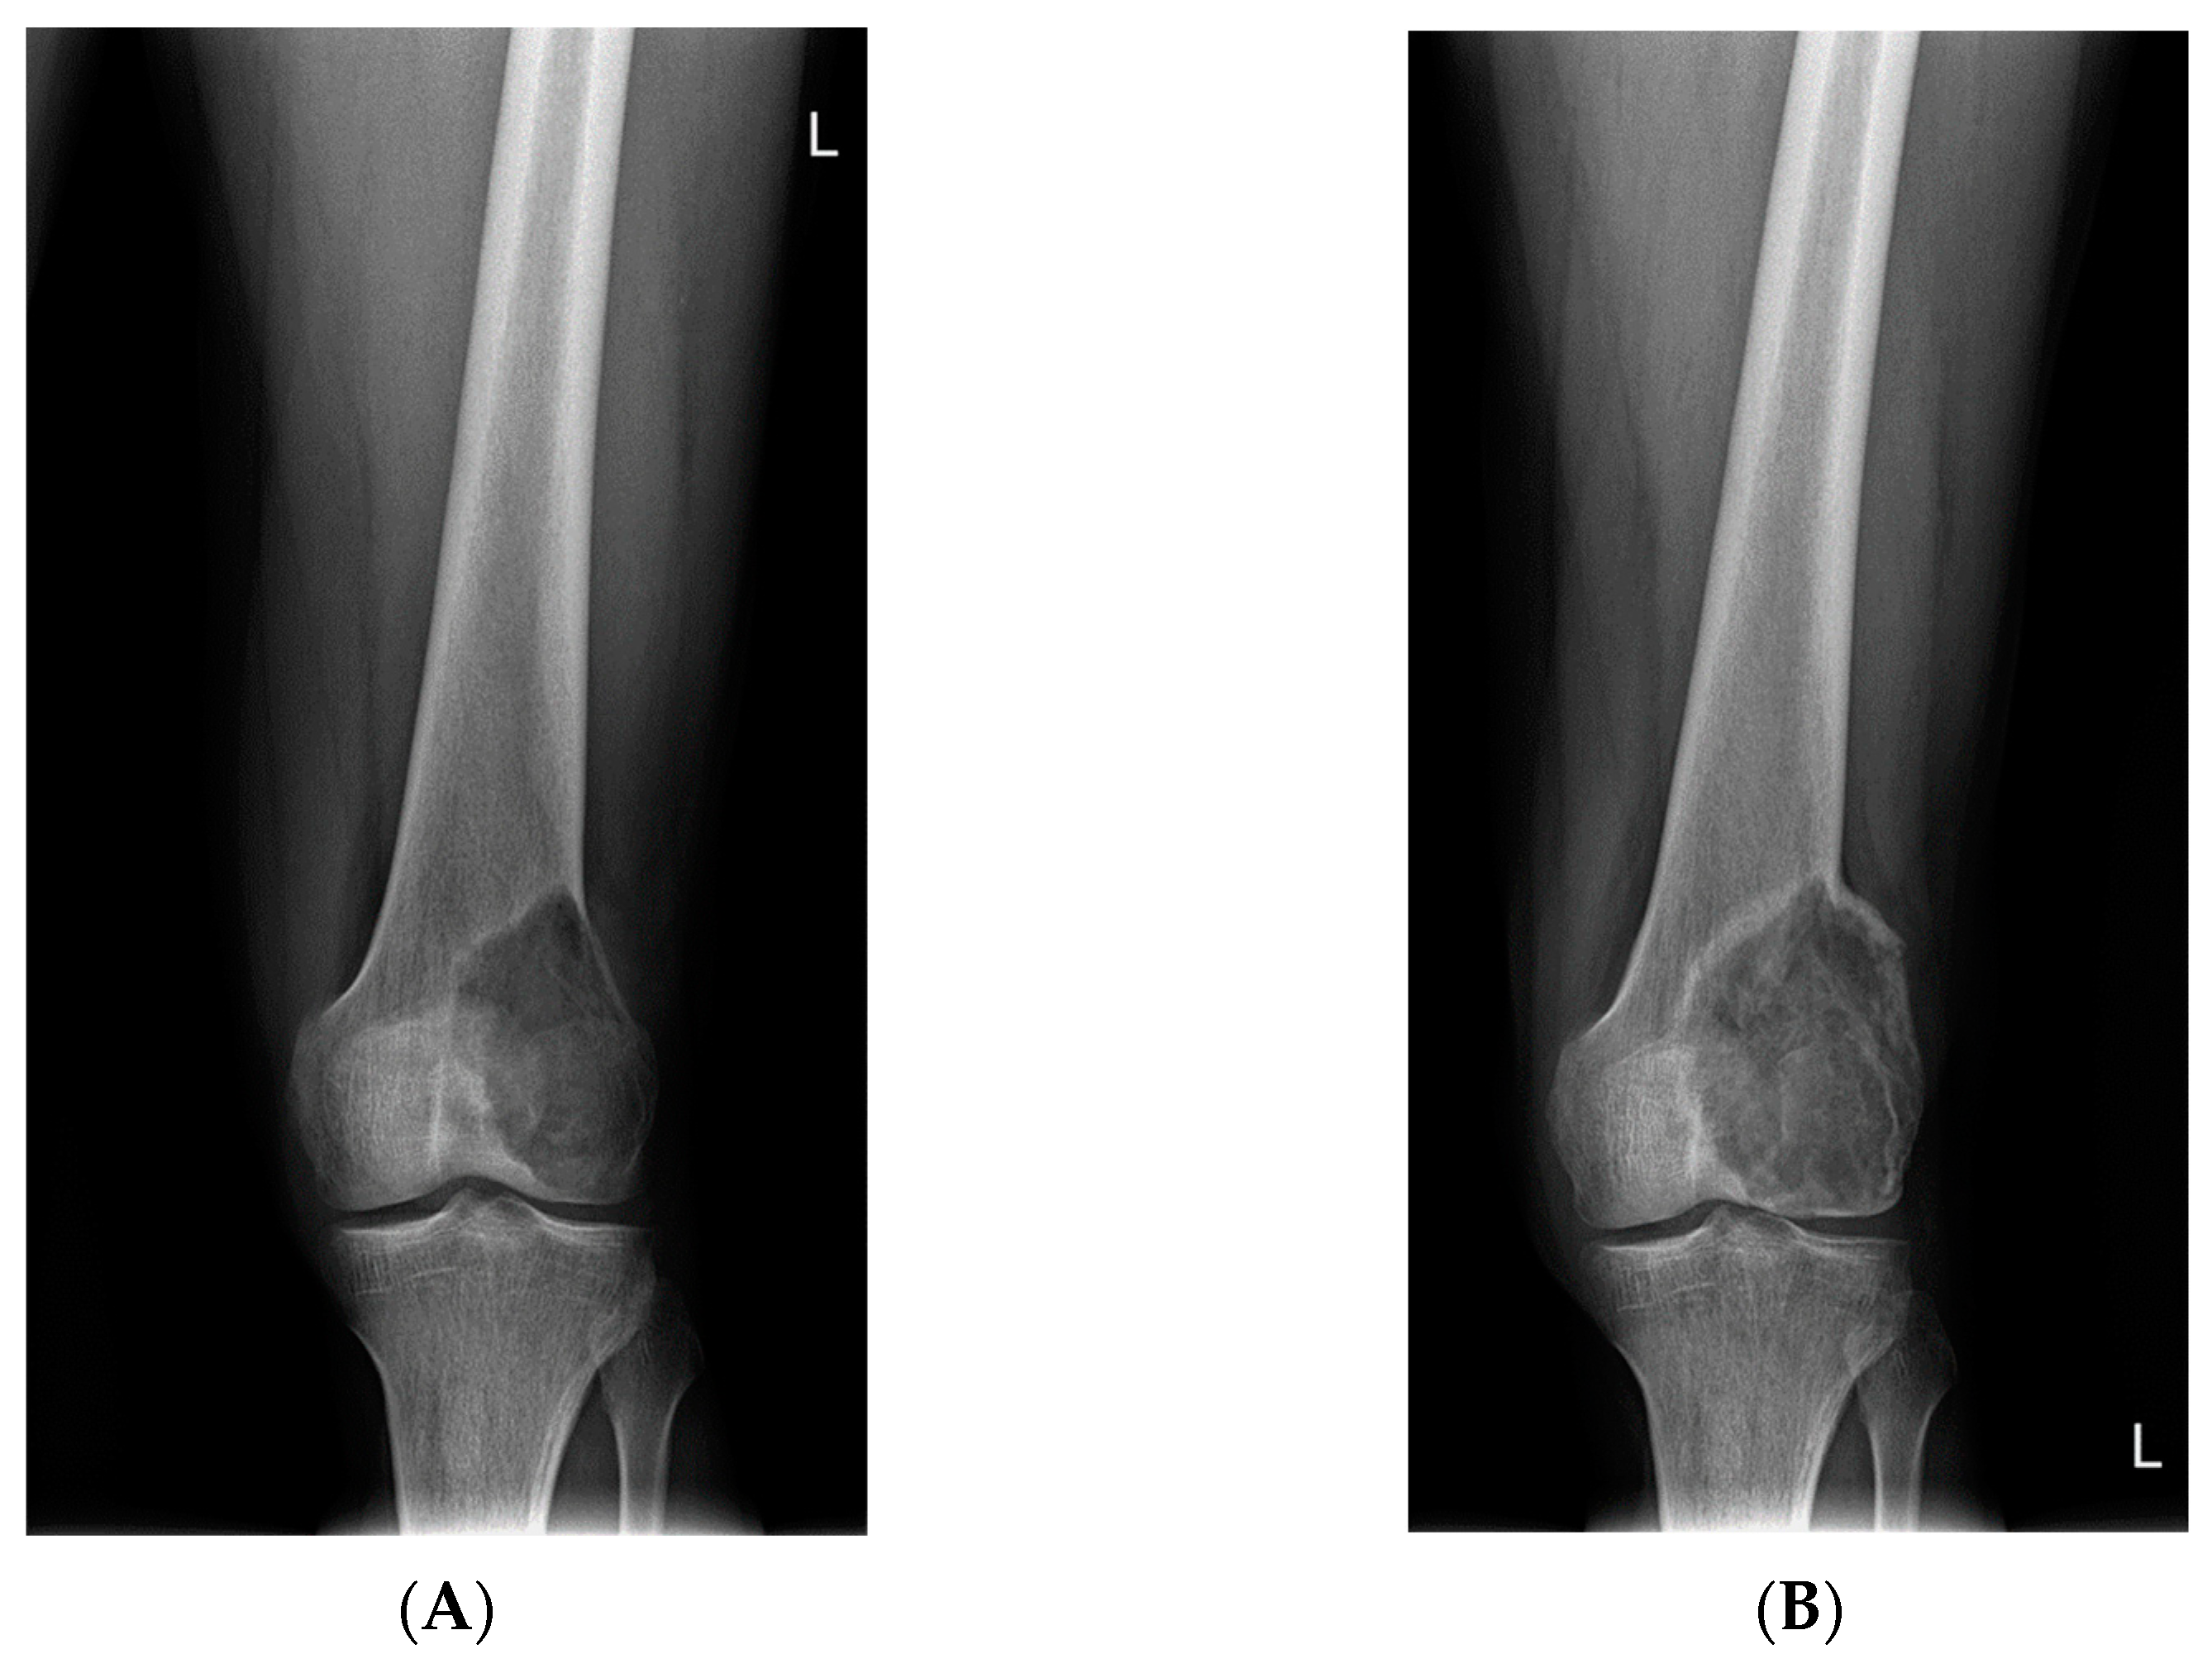

- Van Langevelde, K.; McCarthy, C.L. Radiological findings of denosumab treatment for giant cell tumours of bone. Skelet. Radiol. 2020, 49, 1345–1358. [Google Scholar] [CrossRef] [PubMed]

- Murphey, M.D.; Nomikos, G.C.; Flemming, D.J.; Gannon, F.H.; Temple, H.T.; Kransdorf, M.J. Imaging of Giant Cell Tumor and Giant Cell Reparative Granuloma of Bone: Radiologic-Pathologic Correlation. RadioGraphics 2001, 21, 1283–1309. [Google Scholar] [CrossRef]

- Oguro, S.; Okuda, S.; Sugiura, H.; Matsumoto, S.; Sasaki, A.; Susa, M.; Morioka, H.; Jinzaki, M. Giant Cell Tumors of the Bone: Changes in Image Features after Denosumab Administration. Magn. Reson. Med. Sci. 2018, 17, 325–330. [Google Scholar] [CrossRef]

- Hakozaki, M.; Tajino, T.; Yamada, H.; Hasegawa, O.; Tasaki, K.; Watanabe, K.; Konno, S. Radiological and pathological characteristics of giant cell tumor of bone treated with denosumab. Diagn. Pathol. 2014, 9, 111. [Google Scholar] [CrossRef]

- Veng, C.; Jørgensen, P.H.; Krog-Mikkelsen, I.; Stilling, M. Measurement of bone mineral density as an efficacy marker in denosumab treatment of giant cell tumour of bone. BMJ Case Rep. 2017, 2017, bcr2017220369. [Google Scholar] [CrossRef] [PubMed]